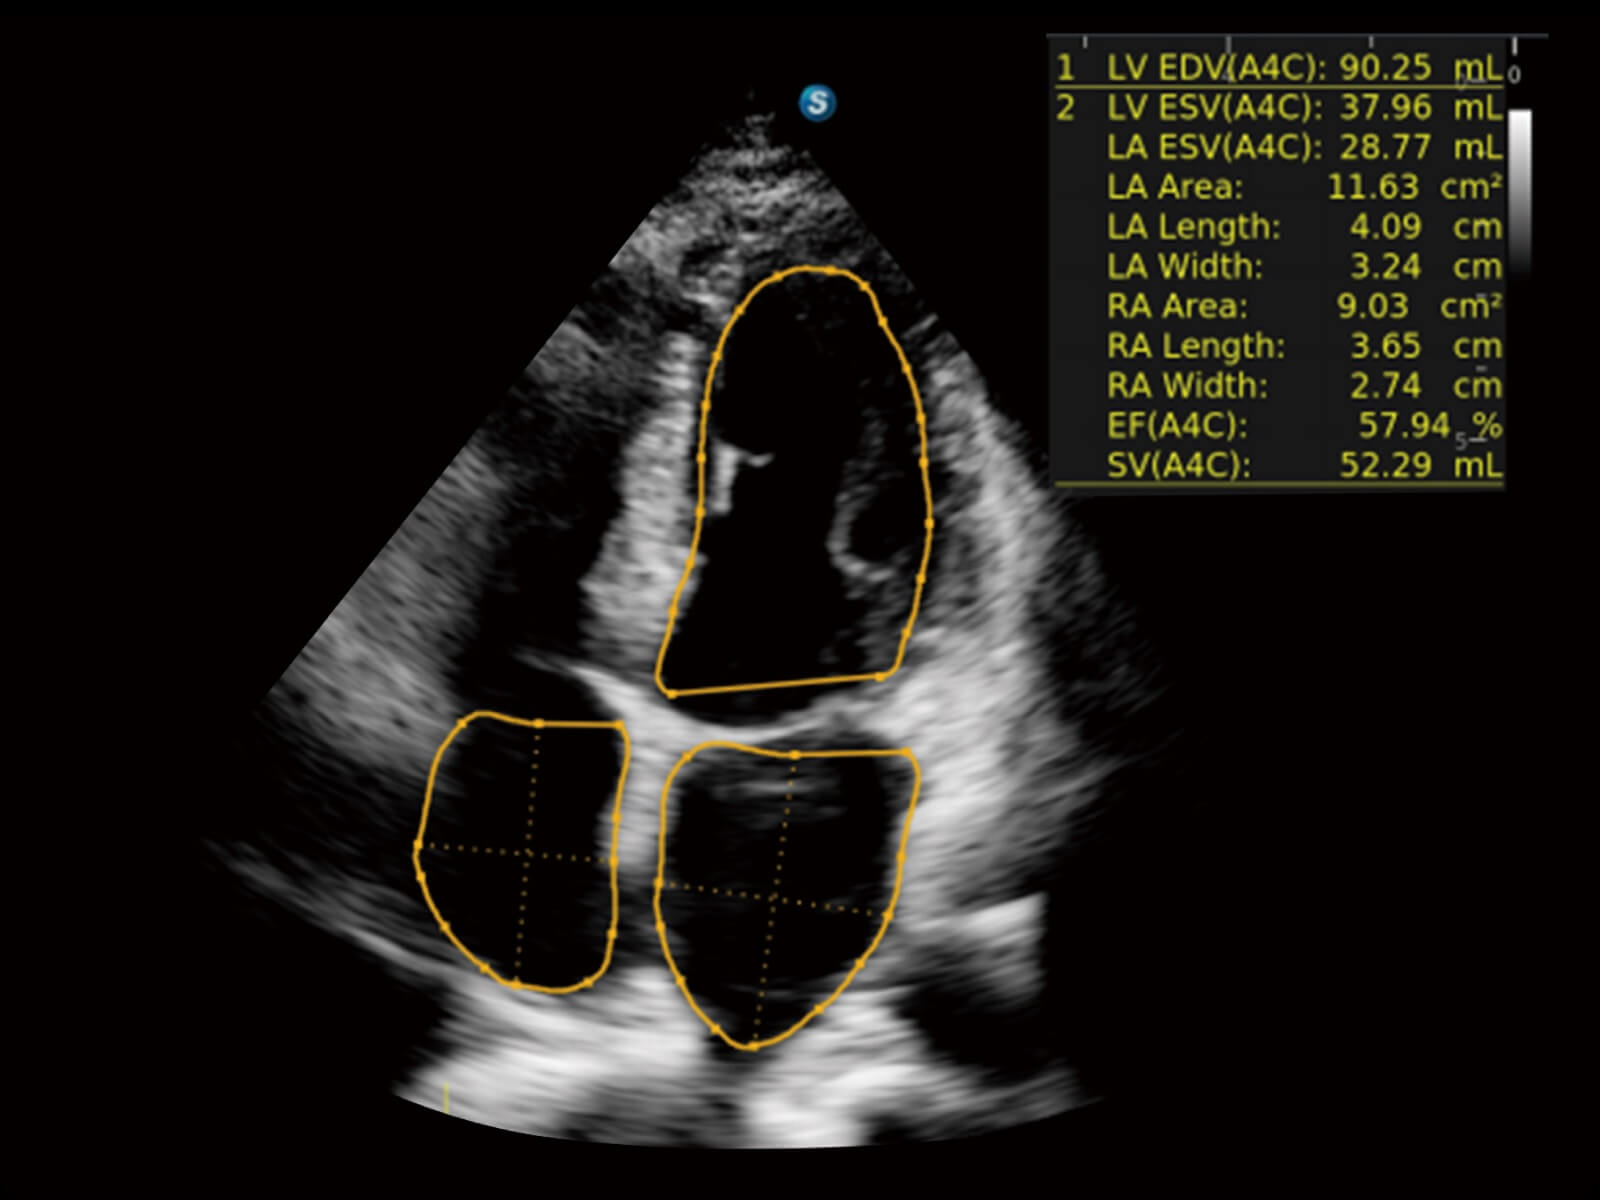

• 心脏应用

临床图

心脏组织多普勒成像

心脏解剖M型成像